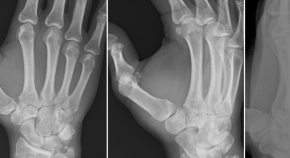

Bildgebung der Hand